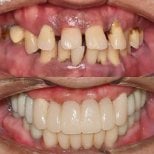

- Check reviews and patient photos. Look for real before-and-after cases and feedback from international patients.